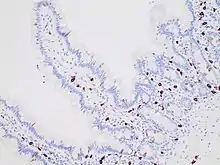

Micrograph of mastocytosis. Skin biopsy. H&E stain.

Immunohistochemistry for c-KIT highlights mast cells (darkly stained) in the mucosa of the small intestine.